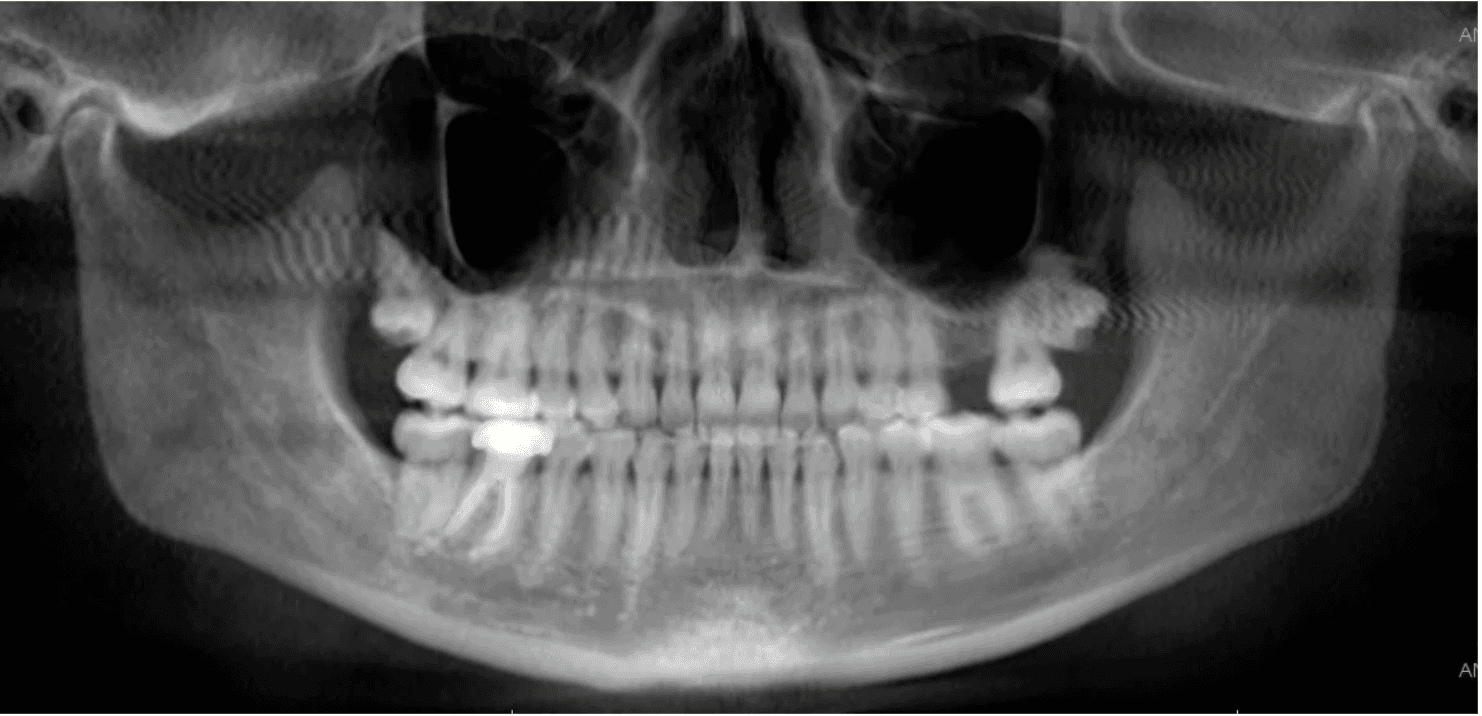

X-RAYS